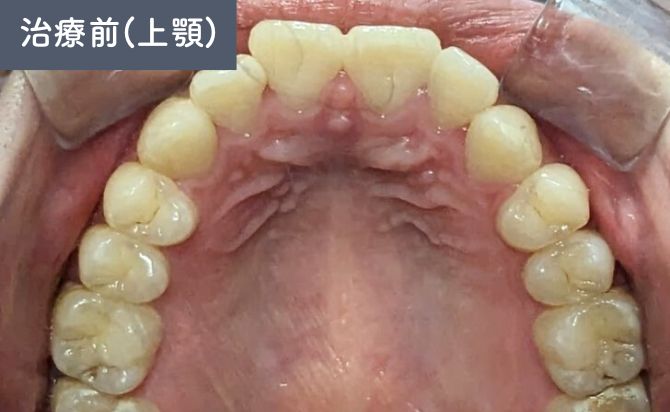

歯並びの変化(上)

口元の評価では、上顎前歯の前方位が認められ、軽度〜中等度の上下顎前突(出っ歯) が確認されました。

前歯の傾斜が強く、上唇の突出感にも影響していましたが、歯列全体のスペース不足は軽度であり、非抜歯での整列および前方位の改善が可能な状態 と判断しました。